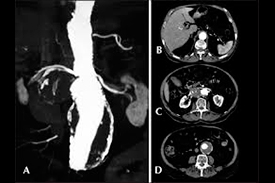

Aneurismas arteriais: São dilatações das artérias que podem evoluir para ruptura e sangramento ou, menos frequentemente, trombose da artéria dilatada. O cirurgião vascular trata os aneurismas de aorta, das artérias dos membros e das artérias viscerais. São geralmente assintomáticos durante seu crescimento, caracterizando importante fator de preocupação visto que podem ser descobertos somente no momento da ruptura, o que diminui muito a possibilidade de correção e prevenção de hemorragia fatal nos aneurismas da aorta, por exemplo.